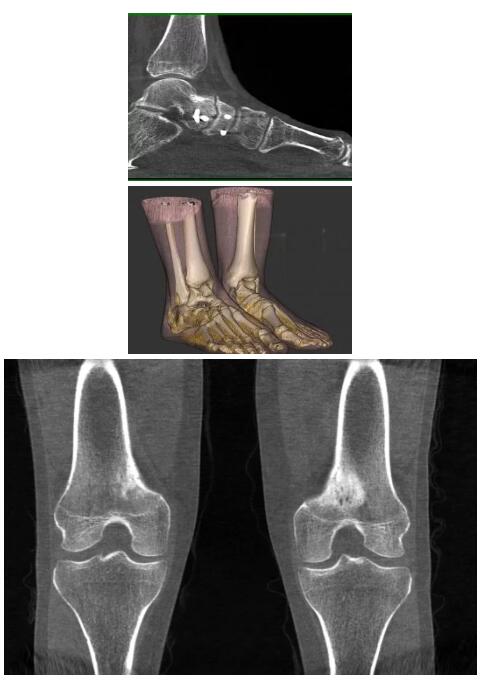

比如上面這款專用于足部和踝部掃查的CT成像系統(tǒng),患者在進行CT掃查時只需要站在上面即可,雙腳站或者單腳站都可以,當然,如果患者不是那么方便站著做完CT掃查,也可坐在上面。

這款CT掃查系統(tǒng)自帶屏蔽裝置,它的體積非常小,僅需要極小的空間即可,并不像常規(guī)CT那樣需要一間單獨的檢查室。此外,這種CT掃查的速度非??欤瑑H需30秒左右可以完成檢查,輻射劑量相對常規(guī)的CT要少許多,尤其適合醫(yī)院的骨科使用。

而患者站著做足部或者踝部做CT檢查還有個好處是,可以檢查患者在負重的情況下,骨關節(jié)的真實情況,而躺著做CT掃查時未必能看出來。負重CT掃查特別是對于受傷的運動員或者舞蹈員來說意義更大,能夠更準確地評估傷情,幫助他們盡早復原。

以下是這些“特立獨行”的CT所拍出來的圖像: